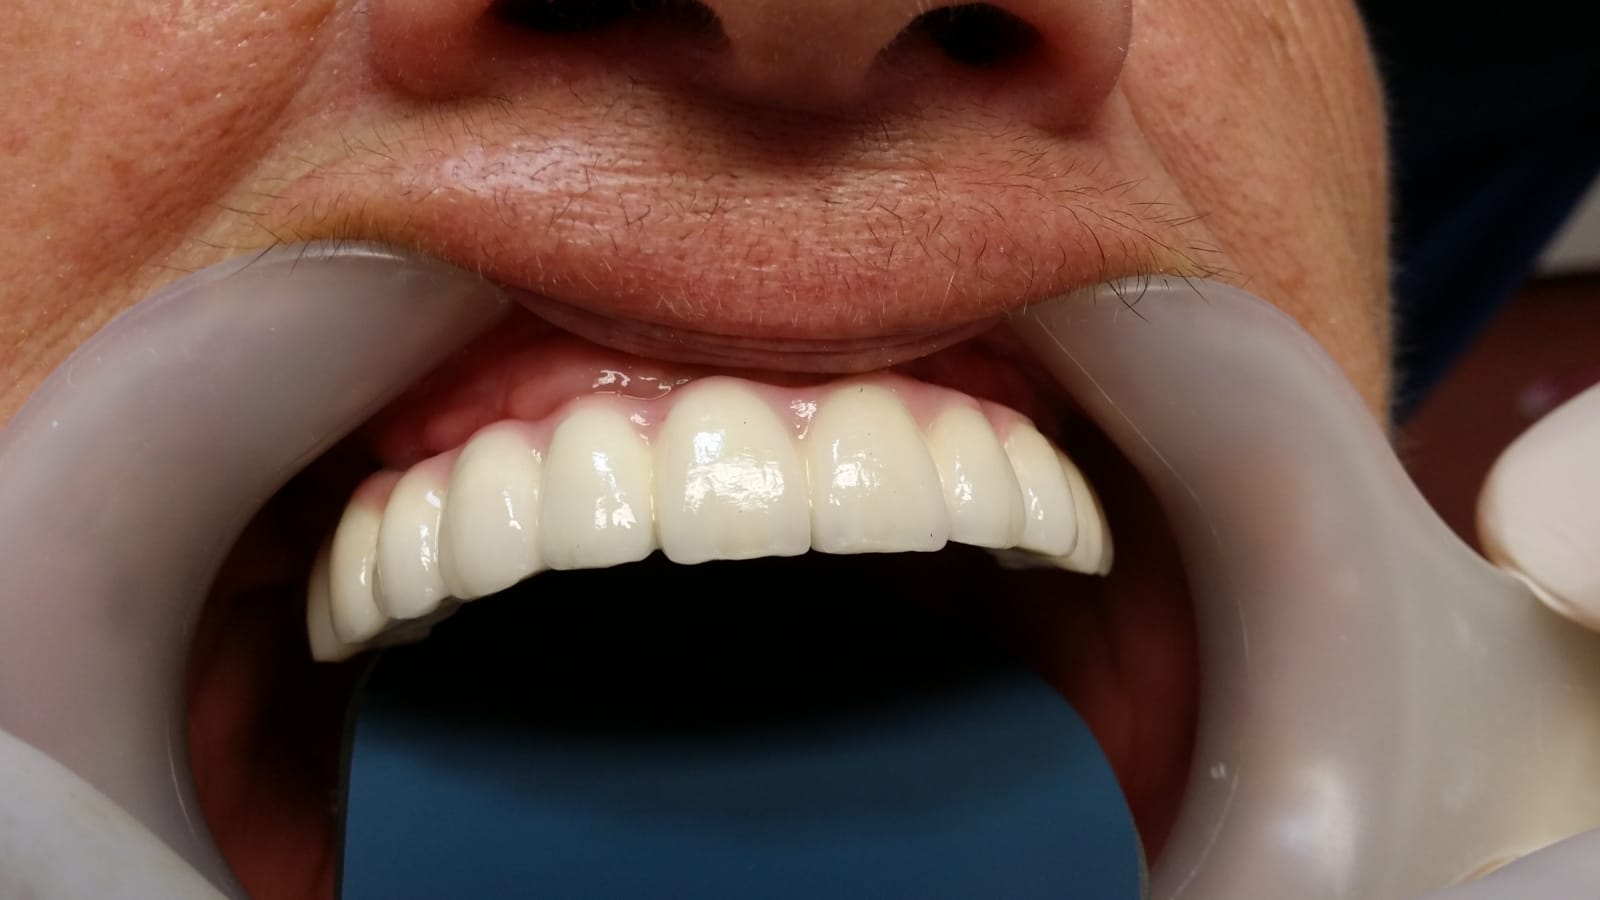

Punte fixa provizorie realizată la mandibula în 24 ore, pe 4 implanturi dentare

Fast and fixed definitiv

Fast and fixed provizorii